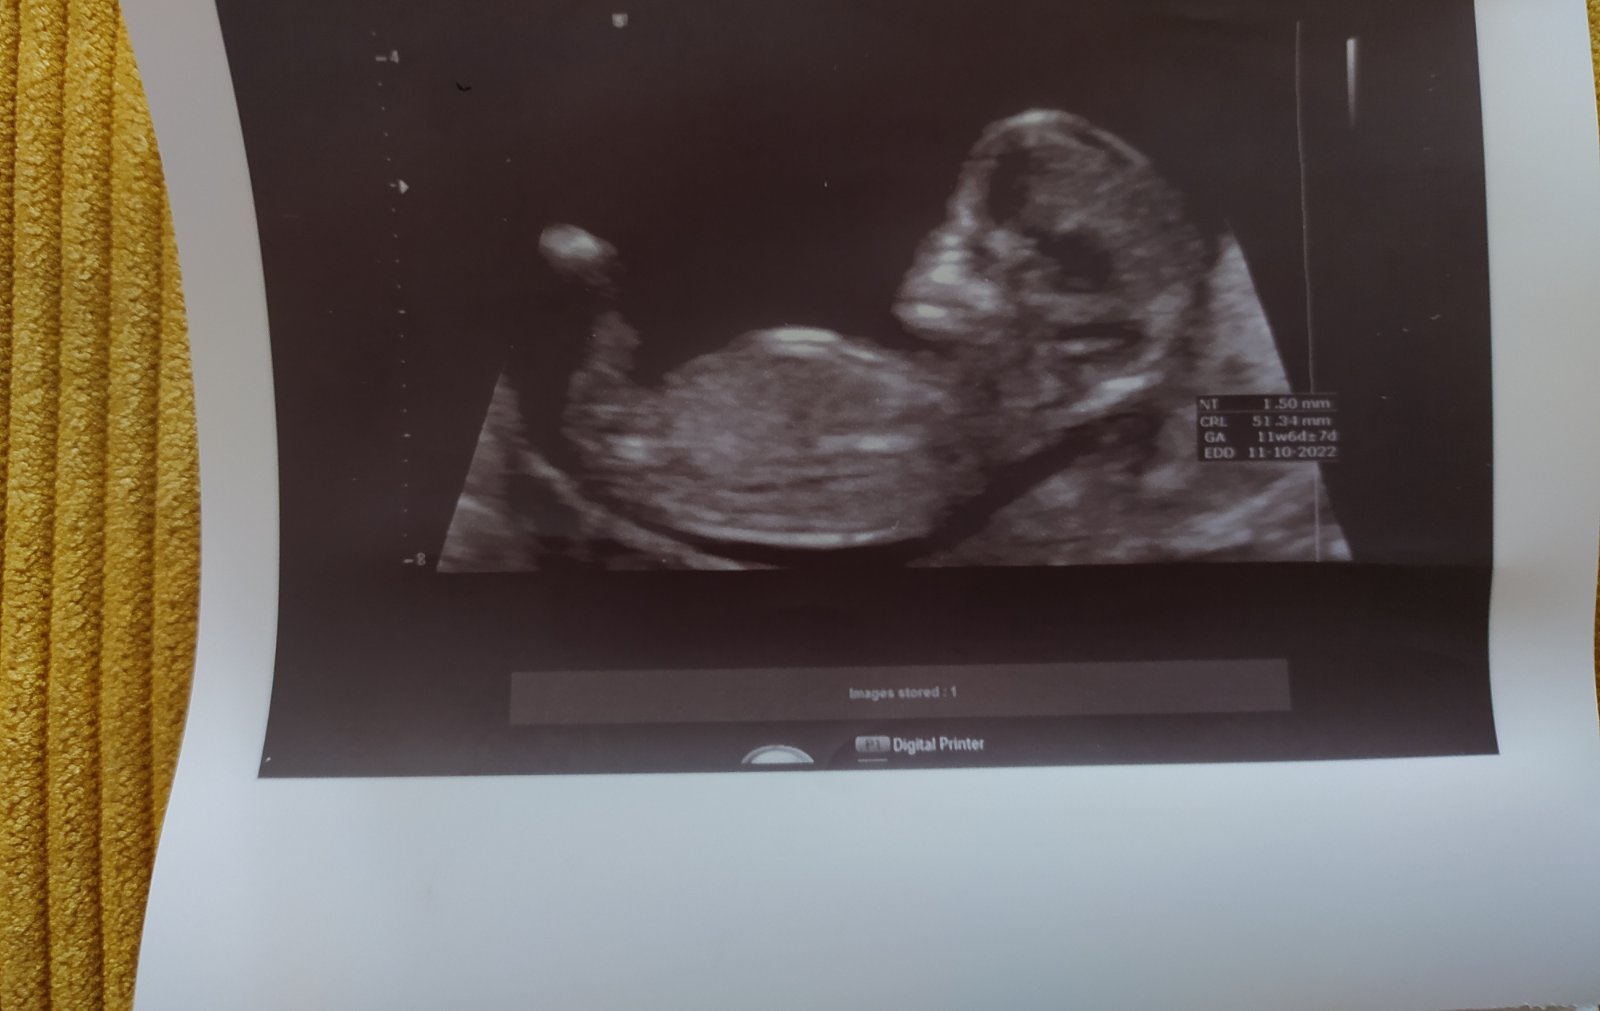

četla jsem, že se dá prý zjistit pohlaví podle fotky z ultrazvuku. Věděl byste alespoň tipnout, podle mé fotky z ultrazvuku, pohlaví?

Foto z 11+6tt 🤰.

bohužel nelze to říci, na snímku není dostatečně zachycená patřičná oblast. 😁